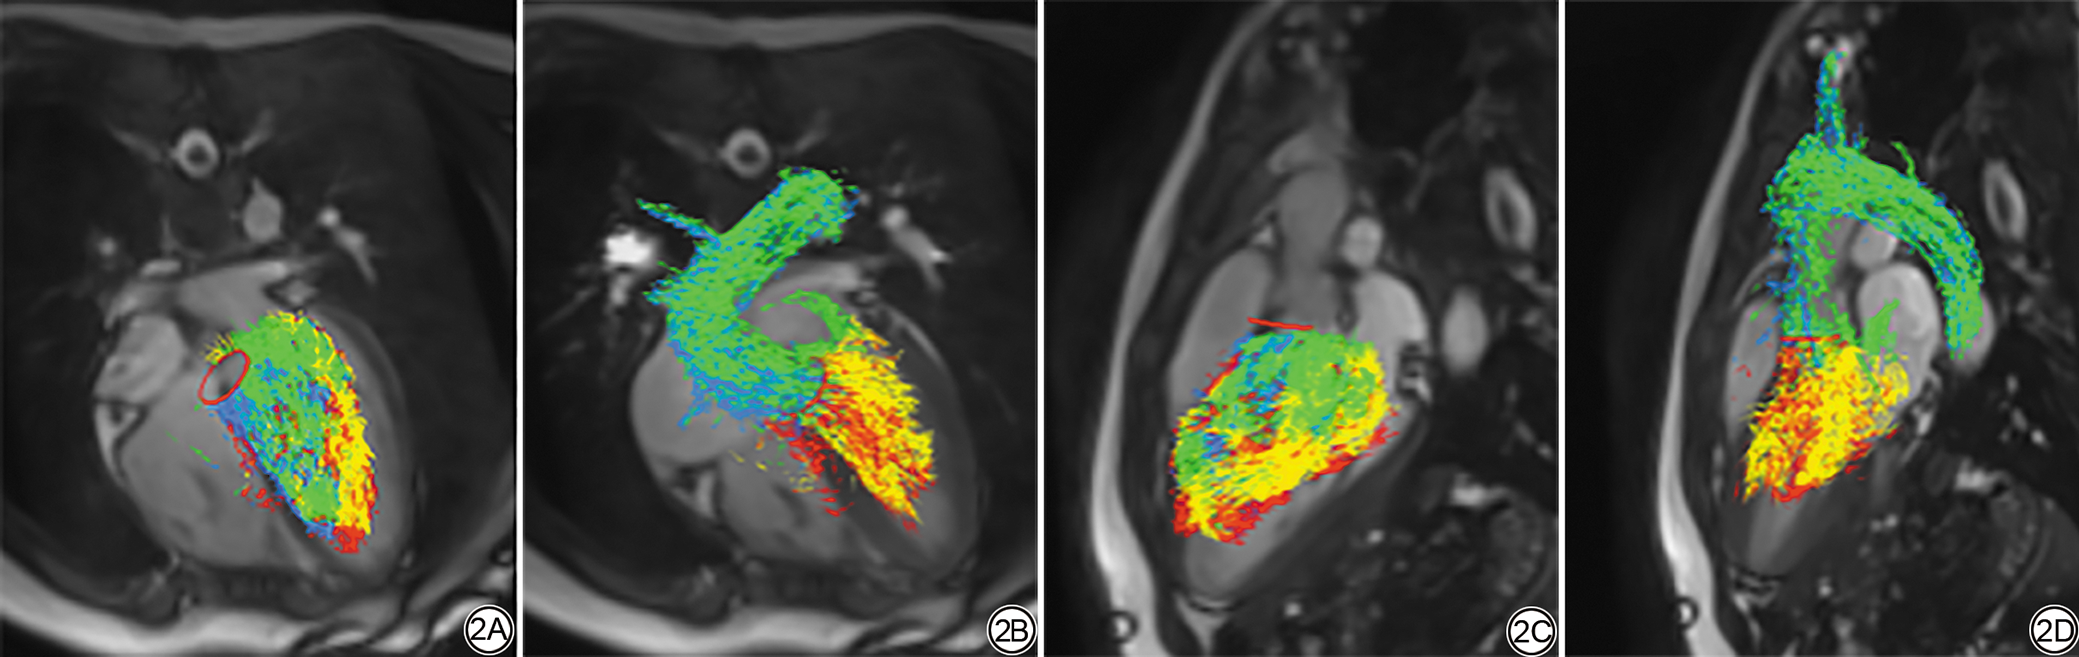

对照组和PVCs组左心室血流可视化结果见表3图2图3。血流成分方面,PVCs组直接血流低于对照组(P=0.045)。与PVCs-M组相比,PVCs-S组剩余容积增加(P=0.016),直接血流减少(P=0.049)。

在左室KE相关参数方面,PVCs组与对照组也存在显著差异。与对照组相比,PVCs组的TD增加(P=0.001)。与PVCs-M组相比,PVCs-S组收缩期KEiEDV减少(P=0.003)。

图3  PVCs-S组的患儿左室血流可视化(女,10岁,负荷为11‰的PVCs患儿)。3A、3C:舒张期左室血流分量的路径线可视化。3B和3D,收缩期左室血流分量可视化。直接血流为绿色,占比22.69%%;保留流入量为黄色,占比29.24%;延迟射血为蓝色,占比17.54%;剩余容积为红色,占比30.53%。

Fig. 3  Visualization of left ventricular blood flow in a child in the PVCs-S group (female, 10years, a child with PVCs with a burden of 11‰). 3A and 3C show the pathline visualization of left ventricular blood flow components during diastole; 3B and 3D show the visualization of left ventricular blood flow components during systole. Direct flow is green, accounting for 22.69%; retained inflow is yellow, accounting for 29.24%; delayed ejection flow is blue, accounting for 17.54%; residual volume is red, accounting for 30.53%.